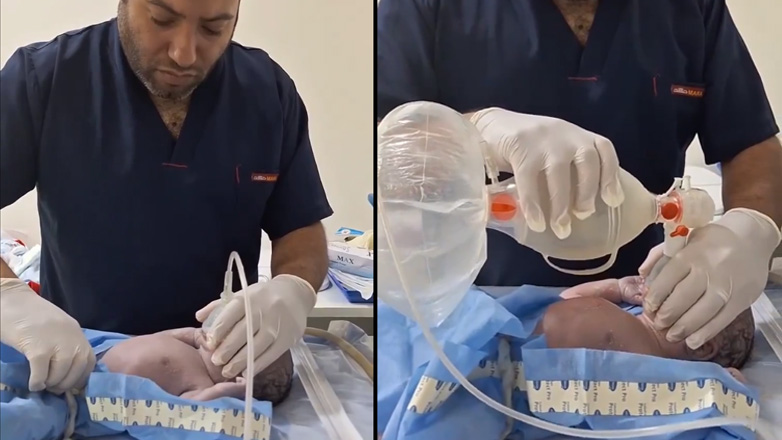

Αχαΐα: Βίντεο-ντοκουμέντα με τους συνεχείς ιατρικούς ελέγχους που υποβλήθηκε το 2ο μωρό

Σε αυτό το βίντεο το μόλις 1 μηνός κοριτσάκι φαίνεται στο κρεβάτι, με τους γιατρούς να είναι από πάνω του και να το εξετάζουν...

27/10/2023 | 17:06